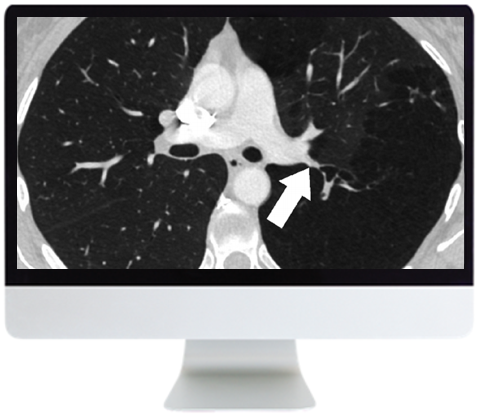

- Discuss key factors in nodule management, management approach focusing on current guidelines, and pitfalls

- Review the spectrum of adenocarcinoma, correlation of CT with pathology, and impact on subsolid nodule management

- Discuss patterns of multiple small nodules, anatomic basis for pattern-based approach, strategies for diagnosis, common causes, and more rare considerations

- Management of Solid Pulmonary Nodules: Characterization and Update—J. Ko

- Adenocarcinoma and the Subsolid Nodule: Current Concepts—J. Ko

- Nodular Pattern on Chest CT—D. Manos